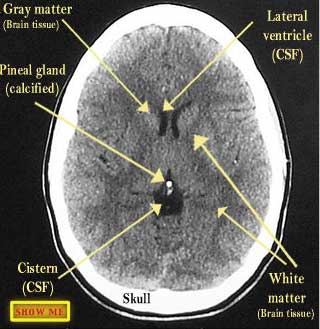

See if you can identify the structures on the right side of the patient's brain.

click to view answer